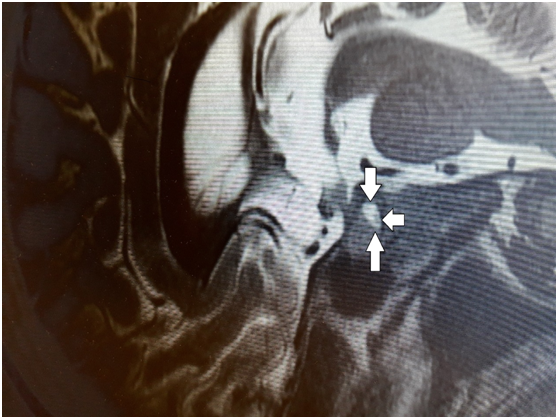

The patient then underwent a brain CT scan, with a 2 cm homogeneously enriched focal lesion emerging in the right frontal lobe, compatible to metastasis, and several smaller scattered in the brain parenchyma. Parallelly, an 8 mm enriched lesion in the pituitary fossa was also depicted, compatible either with a pituitary adenoma or a metastasis. To clarify the nature of the lesion, pituitary MRI was performed, which showed an 8.5 x 6.5 mm mass lesion in the pituitary stalk, which argued for metastatic disease, with hemodynamic pattern similar to the metastasis in the right frontal lobe (Figure 2). The MRI findings confirmed the diagnostic suspicion of central diabetes insipidus, as was shown by the signs and symptoms of the patient (hypernatremia, polyuria, polydipsia, low urine specific gravity), which is a result of hyposecretion of antidiuretic hormone. An increase in prolactin levels, 1115mIU / L (normal levels are less than 500 mIU/L) was also found. Thyroid function and ACTH levels were normal.

Figure 2 Sagittal pre-contrast T1-weighted MR image showing normal pituitary gland with tumor located in the in the pituitary stalk pointed by arrows.